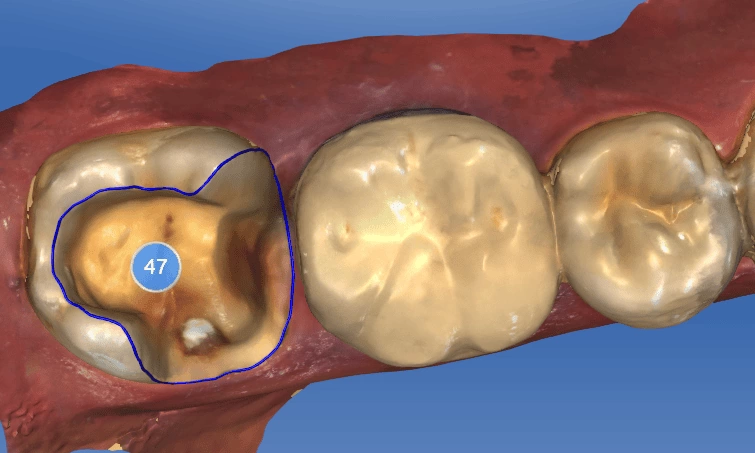

口內掃描取像

- 進行CEREC 3D齒雕口內掃描,經由電腦設計、繪圖及研磨。